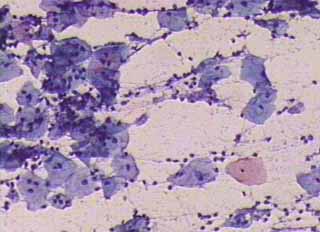

Ιατρικές Εικόνές - Πινακοθήκη κυτταρολογικών ευρημάτων ΙΙΙ

Οι πινακοθήκες κυτταρολογικών ευρημάτων, έχουν σαν στόχο να εμπλουτίσουν την κυτταρολογική εμπειρία σπουδαστών και ειδικευομένων, όπως ένας άτλαντας.

Παρουησιάζονται λοιπόν τυχαία ευρήματα, από το καθημερινό γυναικολογικό ιατρείο.